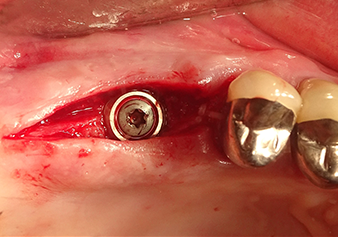

Pour mettre en place le matériau d’augmentation en douceur en direction du sinus maxillaire, l’implant est inséré manuellement très lentement (Fig. 9). Pendant l’opération, la membrane est poussée de nouveau dans la direction crânienne. Au bout de deux mois, le site chirurgical cicatrise sans signes d’irritation. Six mois plus tard, la radio de contrôle révèle une augmentation significative de l'opacité indicative de l’ossification (Fig. 10). La restauration prothétique est réalisée avec une couronne métallo-céramique.

Les augmentations de plancher sinusien interne sont traditionnellement effectuées à l'aide d’instruments manuels, en associant un effet de martèlement à une préparation du site implantaire par des moyens rotatifs. L'expérience a appris à l’auteur que les systèmes piézochirurgicaux modernes rendent cette procédure nettement moins traumatique car l’effet de cavitation permet une utilisation pratiquement sans pression. Les inserts sont utilisés d’une part pour la préparation du site implantaire et pour pratiquer une ouverture minimalement invasive dans le plancher du sinus maxillaire, et d’autre part, pour l’élévation hydrodynamique de la membrane de Schneider [8].

Dans la pratique de l'auteur, l’élévation de la membrane est généralement opérée en deux phases. Mais la technique spécifiée par le fabricant est également adaptée. Dans ce cas, le site implantaire est d'abord préparé et, dans un second temps seulement, une petite ouverture est pratiquée dans le plancher du sinus osseux à l'aide de l'insert Z35P. Grâce à cette méthode particulièrement atraumatique, la patiente n'a ressenti aucune douleur postopératoire et a pu retourner au travail dès le lendemain. Au cabinet de l’auteur, ce résultat est obtenu chez 90 % des patients.